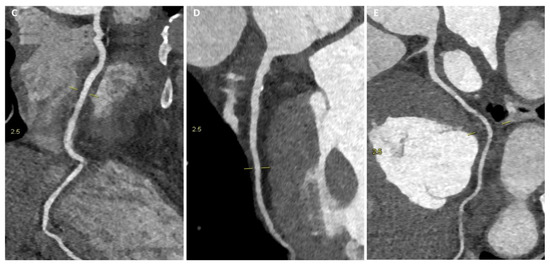

3. Cardiac-CT

3.1. The Added Role

3.2. Morphological and Functional Assessment